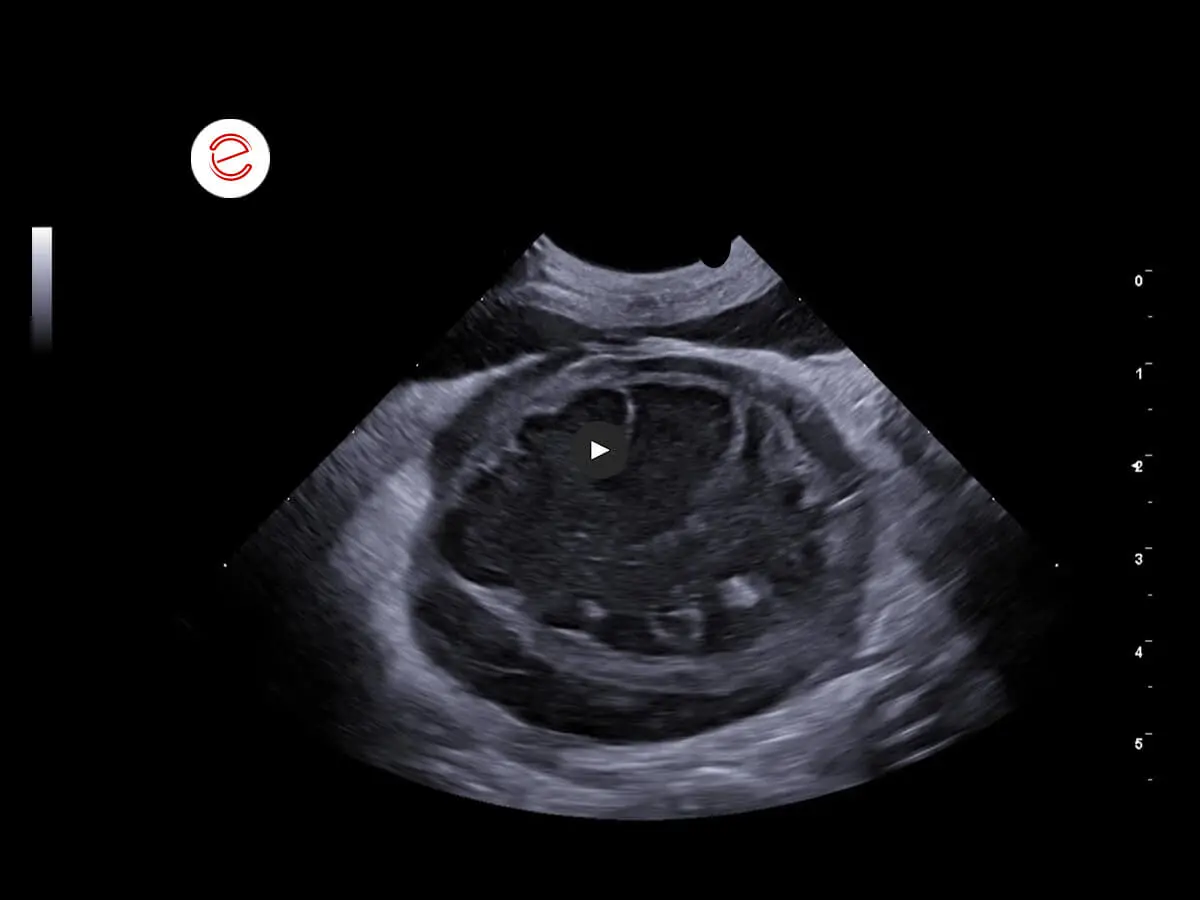

Right kidney: dimensions increased. Margins normal. No cortico-medullary distinction. Diffuse hypo-anechogenicity with findings of a hyperechoic band in which radially developing hyperechoic areas were reported.

The alterations in the right kidney are compatible with a neoplastic infiltrative process in a differential diagnosis with hydronephrosis secondary to a severe inflammatory process. Alterations in the left kidney consistent with severe nephropathy associated with findings of calcifications in differential diagnosis with lithiasis. Diffuse peritonitis also observed. Cytological examination of the right kidney recommended.